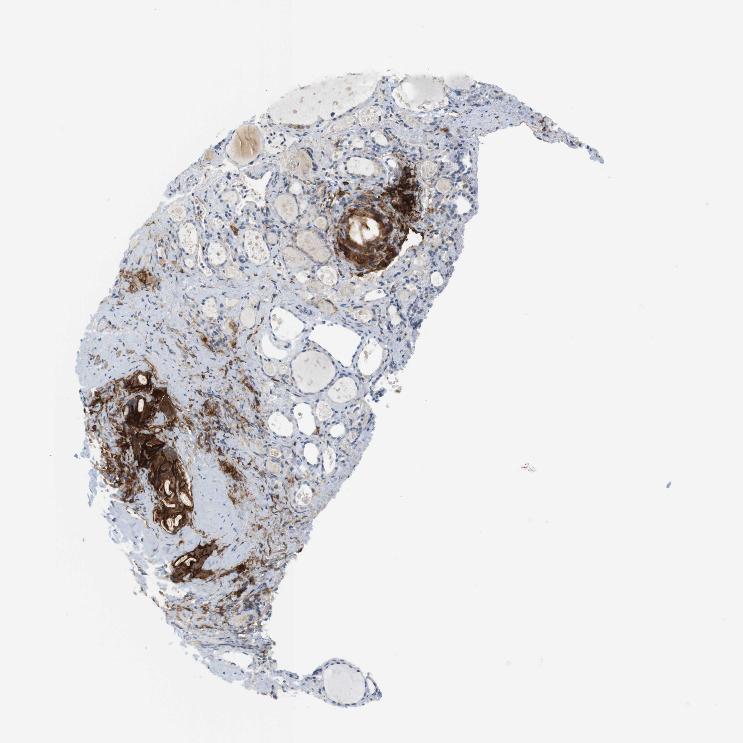

THYROID GLAND - Antibody stainingi

Antibody staining in the annotated cell types in the current human tissue is reported as not detected, low, medium, or high, based on conventional immunohistochemistry profiling in selected tissues. This score is based on the combination of the staining intensity and fraction of stained cells.

Each image is clickable and will lead to virtual microscopy that enables deeper exploration of all samples and also displays staining intensity scores, fraction scores and subcellular localization as well as patient and tissue information for each sample.

Antibody HPA054437Antibody HPA058511Antibody CAB002776Antibody CAB015122

Glandular cells LowNot detectedNot detectedNot detected